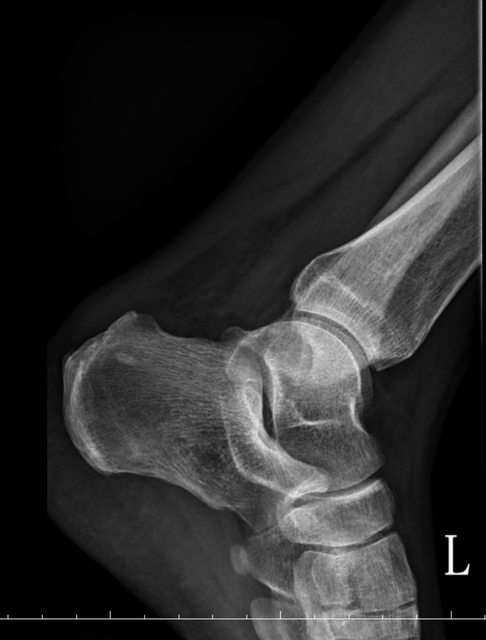

https://i.imgur.com/9HfkOHc.png

https://i.imgur.com/R4JFreK.jpg

醫生似乎很急 就問了二個問題就叫我去照X光 可能就一分鐘吧 回來看了下X光就說可能有神經壓迫 又是14天的消炎止痛藥 說還會痛再來回診或去看脊柱專科或復健科 感覺就是浪費了一天的時間排隊再排隊 沒得到答案 也沒有得到解決... 然後拿了吃越多可能洗腎越快的止痛藥 會不會下次脊柱專科也開14天消炎止痛說如果還有問題叫你去掛神經科? 為何不給我照MRI呢?我第一次去看問了MRI就還是只給我照X光 1.2期X光照了也不一定有異常,我實在不懂不用MRI的邏輯 體驗實在太差了,當然我也知道當有一百號排隊時問診就不可能細到哪怕只有15分 我想不等直接掛看看禮拜三神經科會怎解釋了 ※ 編輯: capybaradash (118.166.44.25 臺灣), 07/31/2023 14:29:17 ※ 編輯: capybaradash (118.166.44.25 臺灣), 07/31/2023 14:37:27

看了下治療方法,那有看等於沒看了 照MRI似乎也是白做,自費照根本浪費 其實X光以我外行人放大好幾倍看過去,左股骨跟大腿骨明顯狀態較差 不清楚醫生是不是有鷹眼,小小一張看過去就說沒什問題 我是不會去考慮手術的 小時候骨折都是看國術館 還減壓股頭打孔...開刀100%NO 治療方法 1.拐杖 2.藥物治療(1)非類固醇類消炎止痛藥(NSAID) (2)口服雙磷酸鹽類藥物 (3)血管擴張劑 (4)高壓氧 目前股骨頭缺血性壞死的治療,根據現有的證據,仍然以手術為主流。 於早期(第一、二期),尚未塌陷的股骨頭缺血性壞死,髖關節減壓手術值得一試, 至於第三、甚至第四期股骨頭缺血性壞死,人工髖關節置換術能夠有效的解除疼痛以及恢 復行走負重的功能。 ※ 編輯: capybaradash (118.166.44.25 臺灣), 07/31/2023 16:04:20